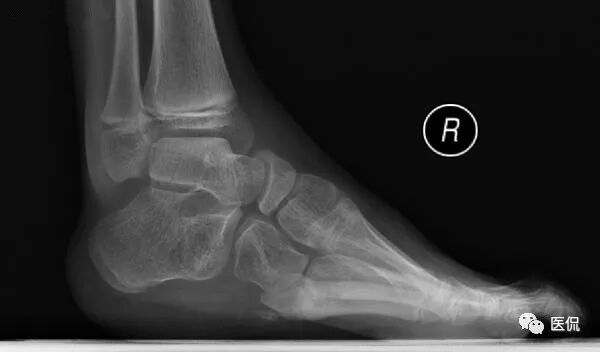

主诉 :主诉:双足内收、内翻畸形,呈马蹄状,且随年龄增长逐渐加重。

现病史:双足明显内翻、内收畸形,跟腱及跖筋膜挛缩、紧张,双足距骨、骰骨均脱位,骰骨外凸形成滑囊,双足跟内翻,尖小,双足背外侧着地负重,内踝深陷,背伸活动功能障碍,不能独立行走,双小腿肌肉萎缩。

本病例临床病史示双足内翻、内收,呈马蹄状,X线整体观及个骨形态的改变与之相对应。负重X线侧位片显示足内弓减小,足外弓增大,舟骨发育不良,距舟关节半脱位,跟距角明显减小。

足部负重侧位片:跟骨马蹄位,其上下径增大;舟骨外侧发育较小,距舟关节半脱位;即使强迫前足向背弯曲,其较后足仍向足底弯曲(弓形足);跟距角变小(正常25-45度),严重时跟骨与距骨中轴线近似平行。